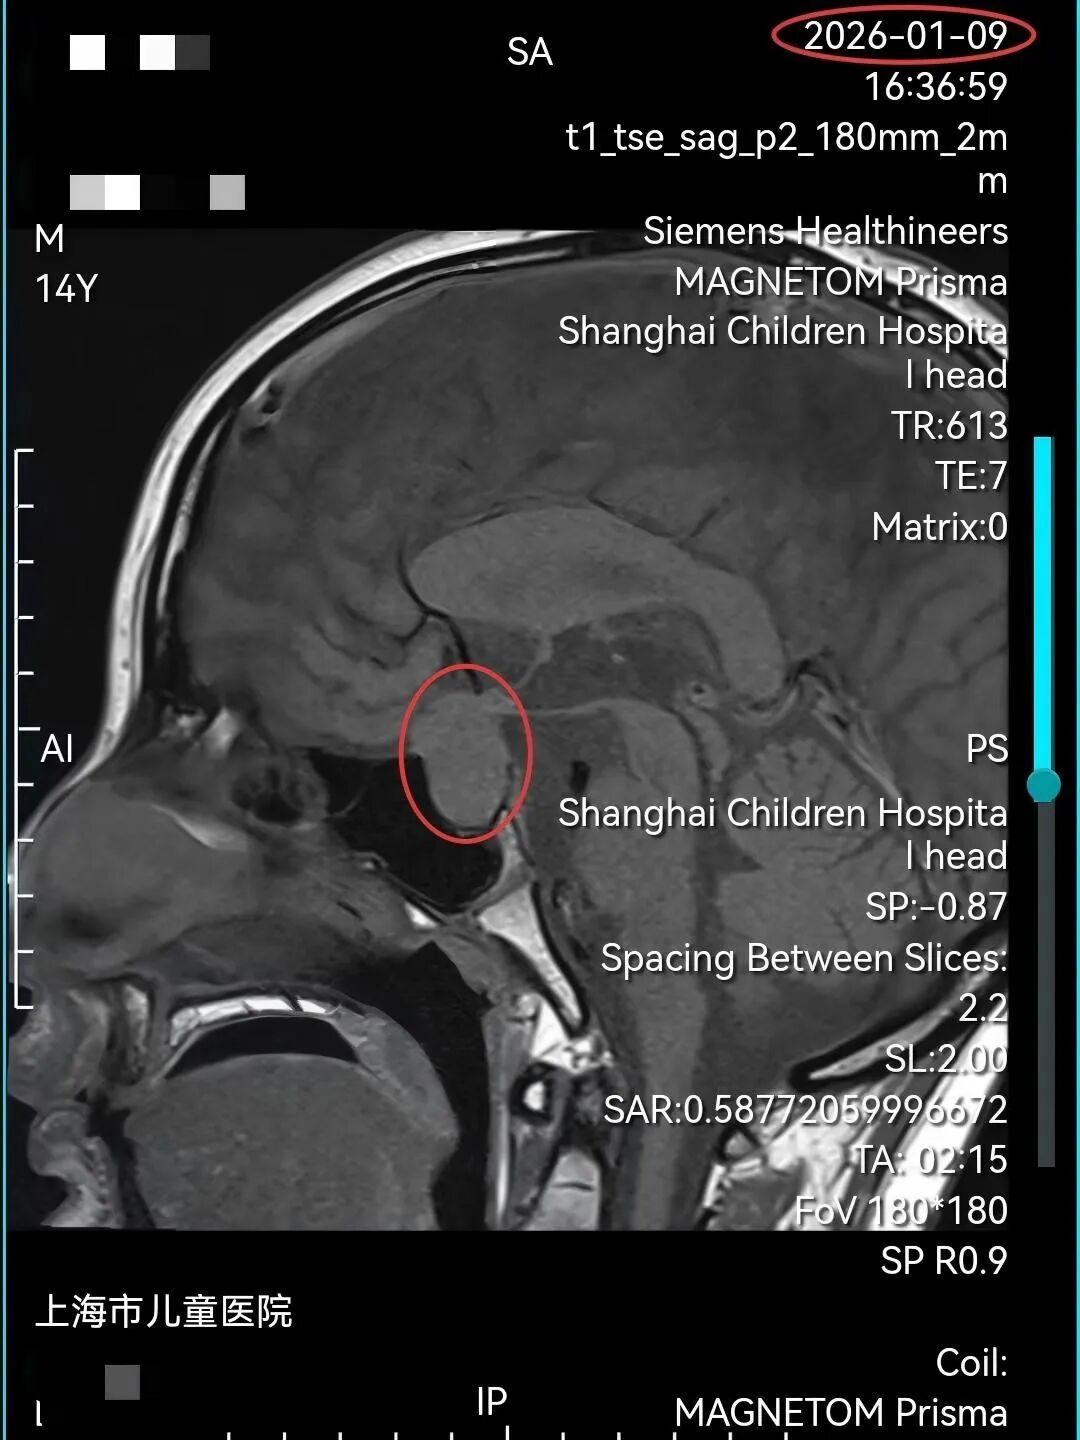

14岁的小易(化名)5年前开始出现多饮、多尿的症状,被诊断为“尿崩症”,近半年来更是头痛欲裂,发作时痛到以头撞墙,左眼瞳孔缩小、眼球转动困难、睁眼困难。家人带着他辗转全国多家知名医院,尝试了多种治疗,但病因始终未明,症状也日益加重。抱着最后一线希望,他们慕名找到了上海市儿童医院内分泌科主任郭盛。郭盛主任在垂体疾病和内分泌肿瘤领域经验丰富,他仔细研读了小易多年积攒的影像资料,凭借深厚的专业功底,敏锐地判断其鞍区很可能存在生殖细胞瘤。

小易被迅速收治入院。鉴于鞍区位置深,毗邻视神经、颈内动脉、垂体、下丘脑等重要结构,且影像评估提示肿瘤已侵袭海绵窦并包绕颈内动脉,手术风险极高,上海市儿童医院第一时间启动了多学科协作(MDT)诊疗模式。

结合细致的影像学判读与多学科综合研判,专家们一致明确诊断为“鞍区生殖细胞瘤伴出血”。面对这一深藏于生命中枢、已局部侵袭关键结构的肿瘤,若采用传统开颅手术,不仅创伤大、风险极高,还会对垂体功能造成不可逆的影响。经过反复论证与审慎评估,在郭盛主任的牵头下,MDT团队最终形成共识:优先采用对生殖细胞瘤高度敏感、且能最大限度保护患儿神经内分泌功能的化疗方案,作为此次治疗的首选策略。

在严密监护下,小易接受了针对性的化疗。令所有人惊喜的是,仅仅3天后复查磁共振(MRI)显示,鞍区的肿瘤病灶已基本消失,之前被肿瘤压迫的垂体得以显露。小易持续多年的剧烈头痛症状完全消失,原本无法睁开的左眼也灵活自如,精神状态大为好转。